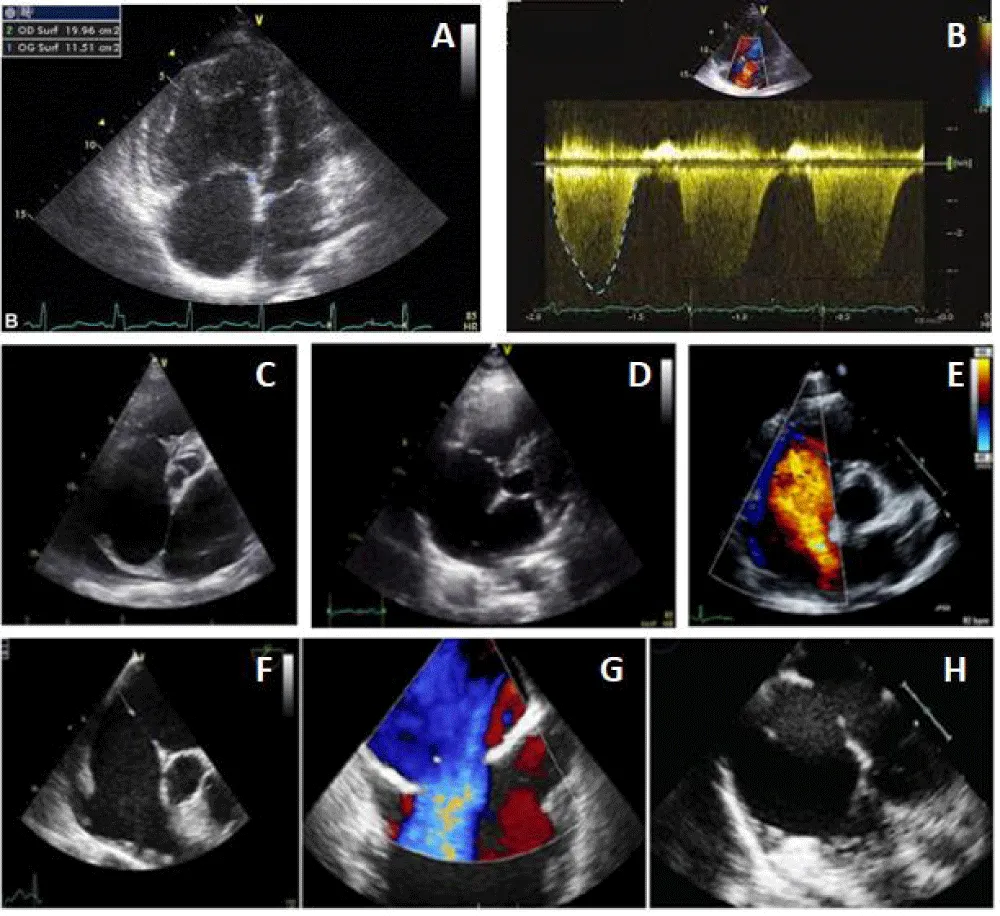

Figure 1: ASD evaluation before the percutaneous procedure. (A: Right cavities dilatation, B: Tricuspid regurgitation, C-D and E: ASD and edges in TTE, F-G, and H: ASD and edges in TEE).

For that, we started by putting the delivery system through the mitral valve in order to increase the support and stabilize the system, then we pushed the prosthesis till the end of its sheath and then we pulled back everything into the left atrium (to avoid trapping the prosthesis in the mitral cords) to deploy the distal disc, brought back into contact with the septum than the proximal disc to thus sandwich the septum between the two discs (Figure 3).

After confirming the correct positioning of the prosthesis and the absence of conflict with the mitral valve, the pulmonary veins, and the superior vena cava, we released successfully the Occluder by anti-clockwise rotation of its rod (Figure 4).